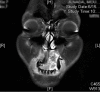

The diagnosis of craniofacial osteosarcoma can be quite challenging, and the condition often goes unrecognized for a considerable period of time. In this report, we discuss the case of a 21-year old woman who presented with a one-year history of a small swelling over the left maxillary alveolar ridge. Upon further investigation, the histopathological examination showed high-grade chondroblastic osteosarcoma. The option of four cycles of neoadjuvant chemotherapy regimen preoperatively was chosen, and left inferior maxillectomy was performed along with reconstruction with obturator prosthesis. This case highlights the difficulties encountered in such rare cases of craniofacial osteosarcomas both in terms of the delay in the establishment of the diagnosis as well as management protocol. A high index of suspicion is required in cases of craniofacial osteosarcoma and early surgical resection with adequate safety margins is warranted.